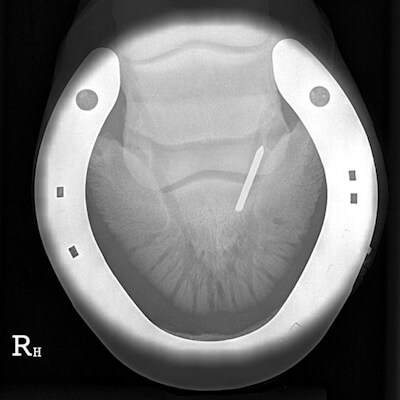

The location of a penetrating injury can be the difference between life and death. Wounds that occur at the back three quarters of the foot are the most serious. Injuries involving the navicular bursa and/or the coffin joint, can result in infection (septic arthritis) if prompt action isn’t taken which can be life-threatening. The further away from the hoof wall an injury occurs, the higher the risk of damage to the coffin (pedal) bone. Infection of the coffin bone (osteitis) causes areas of the bone to die and erode away.

If the infection is deep seated, your vet may need to remove a much larger area of the sole to ensure complete drainage of pus and removal of infected and damaged tissue. If the pedal bone is affected, your vet will need to cut deep into the foot to remove any damaged bone. Radiographs will be needed to ensure all the affected tissue and bone has been removed. Where extensive amounts of sole are cut away, your horse will require a special metal hospital plate attached to the shoe so dressings can be kept in place and kept clean while your horse is recuperating.